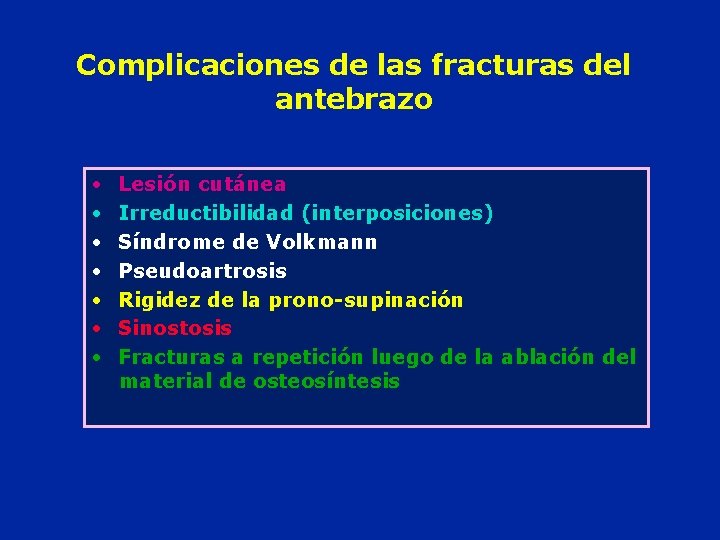

Complicaciones de las fracturas del antebrazo • • Lesión cutánea Irreductibilidad (interposiciones) Síndrome de Volkmann Pseudoartrosis Rigidez de la prono-supinación Sinostosis Fracturas a repetición luego de la ablación del material de osteosíntesis

Cuales son las posibles complicaciones de las fracturas del antebrazo ? • • Lesión cutánea Complicaciones vasculo-nerviosas Irreductibilidad Síndrome de Volkmann Pseudoartrosis Callos viciosos Sinostosis

Cuales son las complicaciones posibles en las fracturas de antebrazo? • Exposición cutánea • • • Complicaciones vasculo nerviosas irreductibilidad Síndrome de Volkmann Pseudartrosis Callo vicioso Sinostosis entre les dos huesos